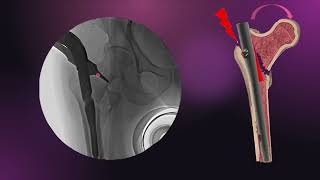

Intertrochanteric Hip Fractures - Everything You...

176.725

9:44